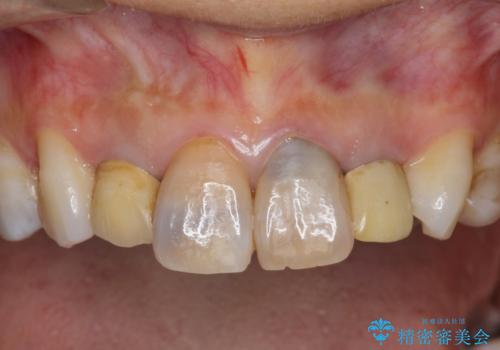

- 「黒ずんで、見栄えの悪い前歯をきれいにしたい。」と、前歯のセラミック治療を希望され来院されました。

全て根管治療のすでになされている歯の変色で、オールセラミッククラウンによる審美性の改善を計画します。

- 52.8万円(ジルコニアクラウン×4・仮歯×4)費用は治療当時の料金となります